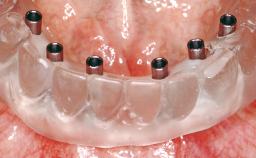

Immediate Loading of Six Implants in the Maxilla and Final Restoration with a Full-Arch CAD/CAM Zirconia FDP

Loading Protocol Immediate

Provisional Implant-Supported Prosthesis Prosthodontic margin < 3 mm apical to mucosal crest Prosthodontic margin < 3 mm apical to mucosal crest